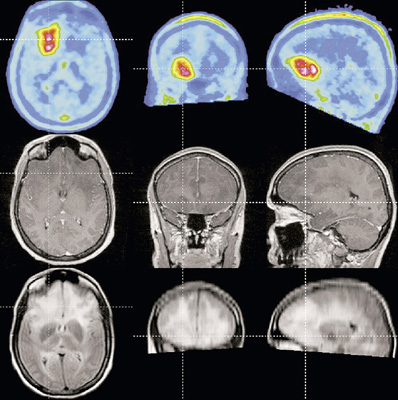

Teljesen új „betekintést” nyújt az emberi agyba a mágnesrezonanciás tomográfiát (MR) és a nukleáris medicina egyik képalkotó eljárását, a pozitron-emissziós tomográfiát (PET) kombináló Siemens-prototípus. Szakértők úgy vélik, hogy ez az egyedülálló új berendezés javítja az Alzheimer-kór diagnosztizálásának lehetőségét a korai szakaszban, valamint az orvosok számára lehetővé teszi a szélütéses (stroke) páciensek állapotának gyorsabb felmérését és a megfelelő terápia meghatározását. A tübingeni egyetem és a memphisi Tennessee egyetem (USA) orvosi karának doktorai a közelmúltban felvételeket készítettek az új berendezéssel az emberi agyról. Az MR technika nagy felbontóképességével és a lágy szövetekről adott éles kontrasztú képeivel járul hozzá a kombinált eljáráshoz, míg a rendkívül érzékeny PET részlet-gazdag képet ad az agy olyan régióiról, melyek fokozott anyagcsere-tevékenységet mutatnak. A prototípust az év második felében tovább tesztelik Németországban.

Eddig a PET technikát használó ideggyógyászok nem tudtak megbízhatóan különbséget tenni kisebb fokú kognitív zavarok és az Alzheimer korai szakasza között. E mellett nem voltak képesek az Alzheimerrel járó agytérfogat-csökkenés egyidejű meghatározására. Az MR/PET révén a vizsgálat egy lépésben elvégezhető. Az orvosoknak a prototípus segítségével más ideggyógyászati rendellenességek – például Parkinson-kór, epilepszia, depresszió és skizofrénia – jobb megfigyelésére és a folyamat fejlődésének felderítésére is módjuk nyílik.

A PET vizsgálat során a páciensbe nagyon kis dózisban radioaktív folyadékot fecskendeznek, amely olyan sejtekben gyülemlik fel és bocsát ki pozitron-sugárzást, amelyeknek megnőtt az anyagcsere-értéke. Amikor a pozitronok elektronokkal ütköznek, megsemmisülnek, és gamma kvantumok keletkeznek. Ezeket a kvantumokat regisztrálja a műszer detektora, amely az adatokból háromdimenziós, rétegelt képet alkot. A Siemens Orvostechnika (Medical Solutions, Med) rendkívül gyors működésű és érzékeny lavina-fotodiódákat alkalmaztak detektorként. Ezek érzéketlenek a tandem berendezés MR-„felének” erős (3 Tesla) mágneses térerejére, amelynek az a nagy, kb. 0,2 mm-es felbontóképességét köszönheti. A két készülék által generált képeket a berendezésben szuperponálják, és így keletkeznek az eddig soha nem látott képek.